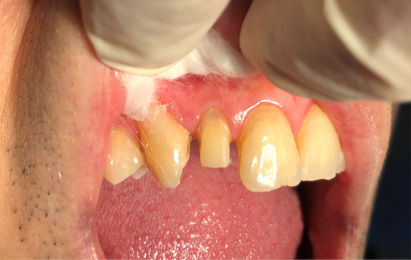

Patient Information: Male, 35 Years Old

8/27/2024,Chief Complaint: Weakness and discomfort in the right maxillary anterior teeth with mastication.

1/6/2025,post placement,tooth preparation,impression taking

1/16/2025: All-ceramic crown restoration for #12; patient asymptomatic